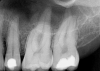

Fig 4. Postoperative final fill.

Figure 4

The 035 final file was used to the 20-mm working length with lubrication. The canal was irrigated with NaCl for 30 minutes, 035 dry points were used, and the root-canal sterilization was performed with the CO2 laser. Then the final fill was completed with the matching 035 gutta-percha and root-canal sealer (Figure 4).